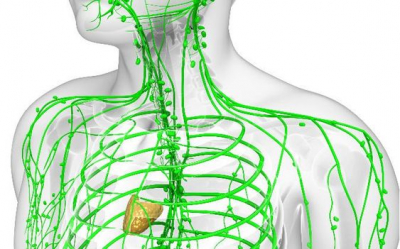

Лимфната система има имунна функция: тя отстранява чуждите частици, бактериите, вирусите и отпадъчните продукти, които попадат в организма.

За разлика от кръвоносната система, лимфната система не разполага със собствена помпа. Лимфата се движи бавно, под ниско налягане, като това движение се дължи на контракциите на мускулите и диафрагмата.

Лимфната система престава да функционира нормално, ако:

- сърдечно и бъбречно заболяване, причиняващо трайно подуване на тъканите

- инфекциозни заболявания

- травми и изгаряния.

Когато всичко е нормално, лимфата изчиства всички отпадни продукти.

5 съвета за подпомагане на лимфната система:

- Пийте достатъчно чиста вода всеки ден, поне 30 мл на 1 кг телесно тегло (това е задължително!).

- Упражнявайте се, правете упражнения и специални тренировки, движете се повече през деня.

- Правете самомасаж със суха четка в посока от периферията към центъра на тялото (движенията трябва да са плавни, меки, без натиск върху лимфните възли).

- Изпълнявайте дихателни упражнения, диафрагмено дишане.

- В допълнение към чистата вода пийте билки (листа от касис, ехинацея, магданоз).

Изводът е прост: водата и движението са живот за лимфата!

За да работи добре лимфната система са й необходими и различни видове витамини и минерали.

Магнезий - отговорен за отпускането и свиването на кръвоносните съдове в кръвоносната система, която включва и лимфните съдове. Магнезият също така предотвратява появата на вазоспазъм.

Витамин В3 (ниацин) - участва в процеса на отпускане на съдовата стена и подпомага циркулацията на кръвта и лимфата.

Витамин С - играе важна роля в укрепването на съдовата стена, като активира производството на колаген и участва в имунната система, която също е тясно свързана с лимфната система.

Витамин D - повишава активността на клетките на имунната система, циркулиращи по лимфните съдове.

Витамин Е - мощен антиоксидант, който предпазва клетките от увреждане.